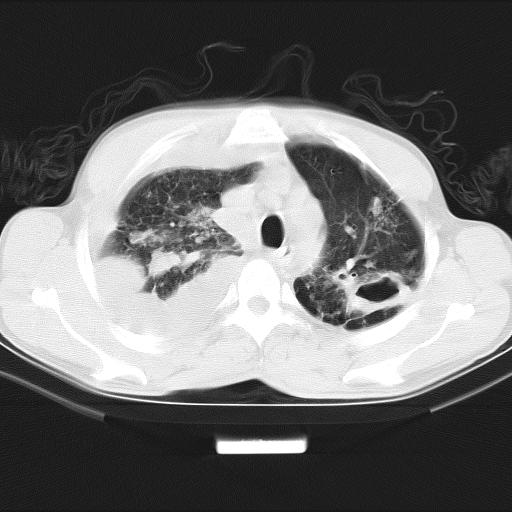

男性,44岁,结核病史多年。现胸闷气短,咳嗽,偶咳血。

1、右侧大量胸腔积液伴右肺压缩性膨胀不全,建议抽液治疗后复查 2、两肺继发性tb伴空洞形成。

1)两肺继发性肺结核伴空洞形成,左肺多发性结核球。2)右侧大量胸腔积液伴右肺部分膨胀不全。3)纵隔淋巴结肿大。

1,双肺多发结节 并空洞影改变, 左侧胸腔积液并部分包裹, 结合原病史首先考虑结核. 但也不除外其它.

2,左侧有一根肋骨陈旧性骨折? 建议追查 .